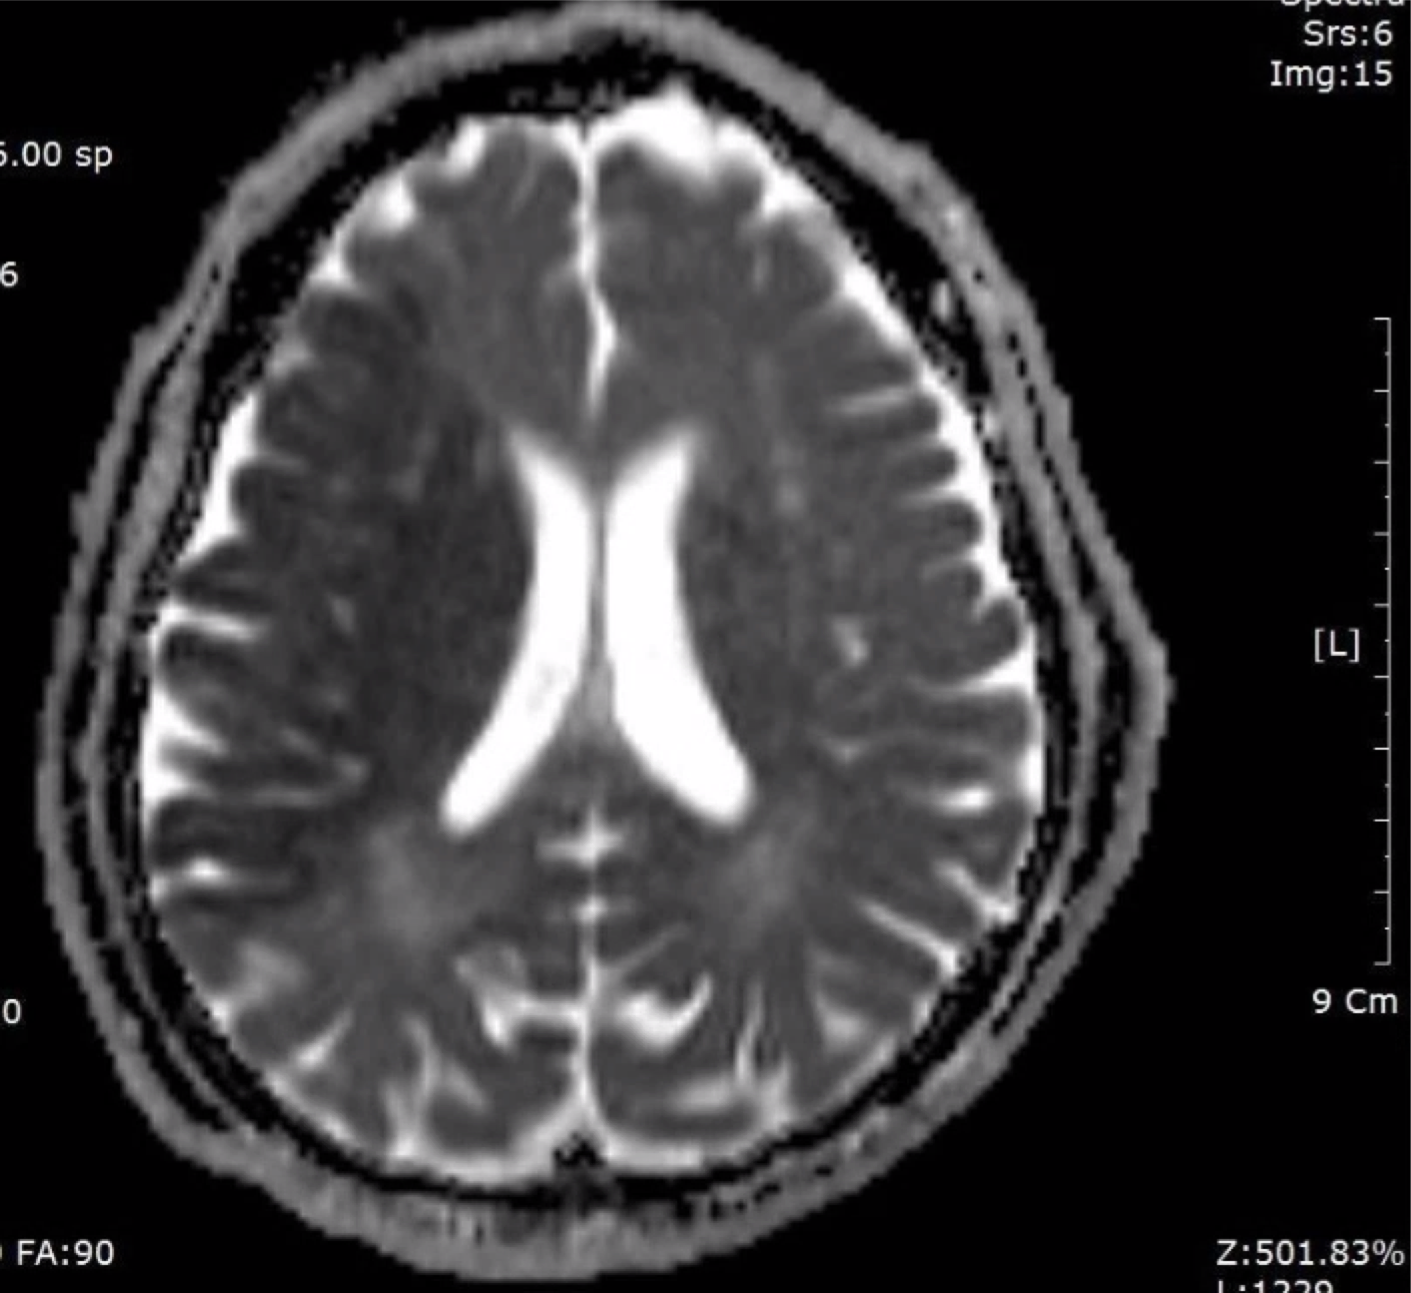

F/73

left hemiplegia due to cerebral infarction 2016.9.16.

cognitive impairment

vascular dementia